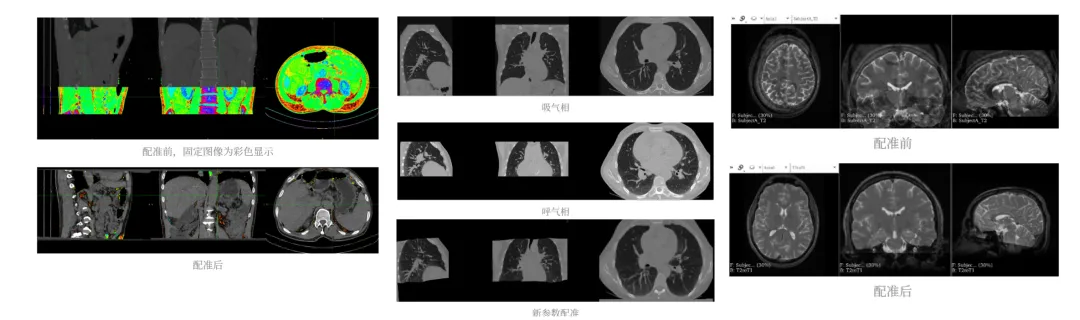

数据格式转换、图像配准与批量处理:DICOM批量转换、ANTS/Elastix多模态配准、Python脚本批量分割,打通数据处理全链路。